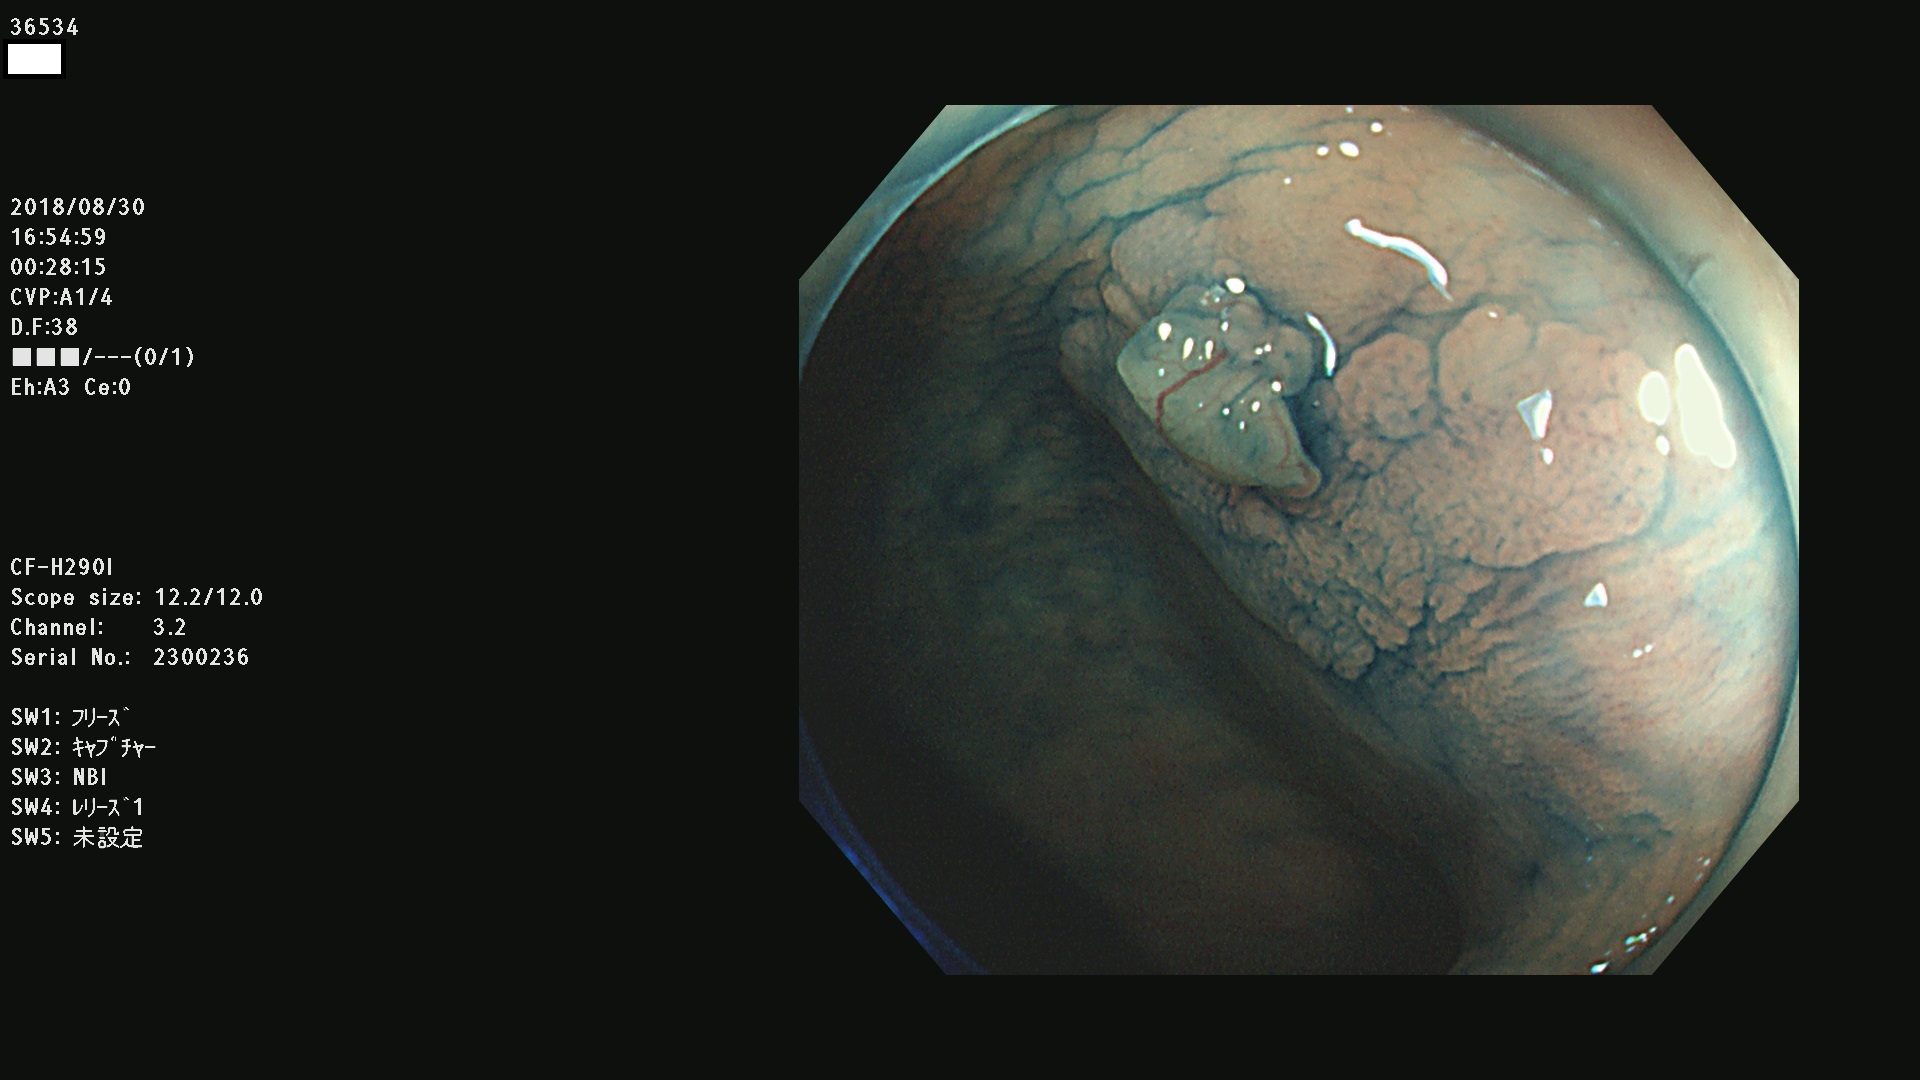

36500 36503 36504 36505 36507(SSAPのみ) 36508 36509 36510 36511 36514 36515 36517 36518 36520 36522(SSAPのみ) 36523 36524 36526 36528 36530 36531 36532 36533 36534 36535 36536 36538 36541 36542 36543 36544 36545 36546 36548 36550 36551 36554 36555 36556 36558 36559 36560 36561 36564 36565 36567 36568 36570 36572 36573 36574 36575 36576 36577 36578 36579 36580 36582 36584 36586 36591 36592 36593 36594 36595 36596 36597 36598

発見困難で危険性の高い平坦型病変(上記100名より抽出)